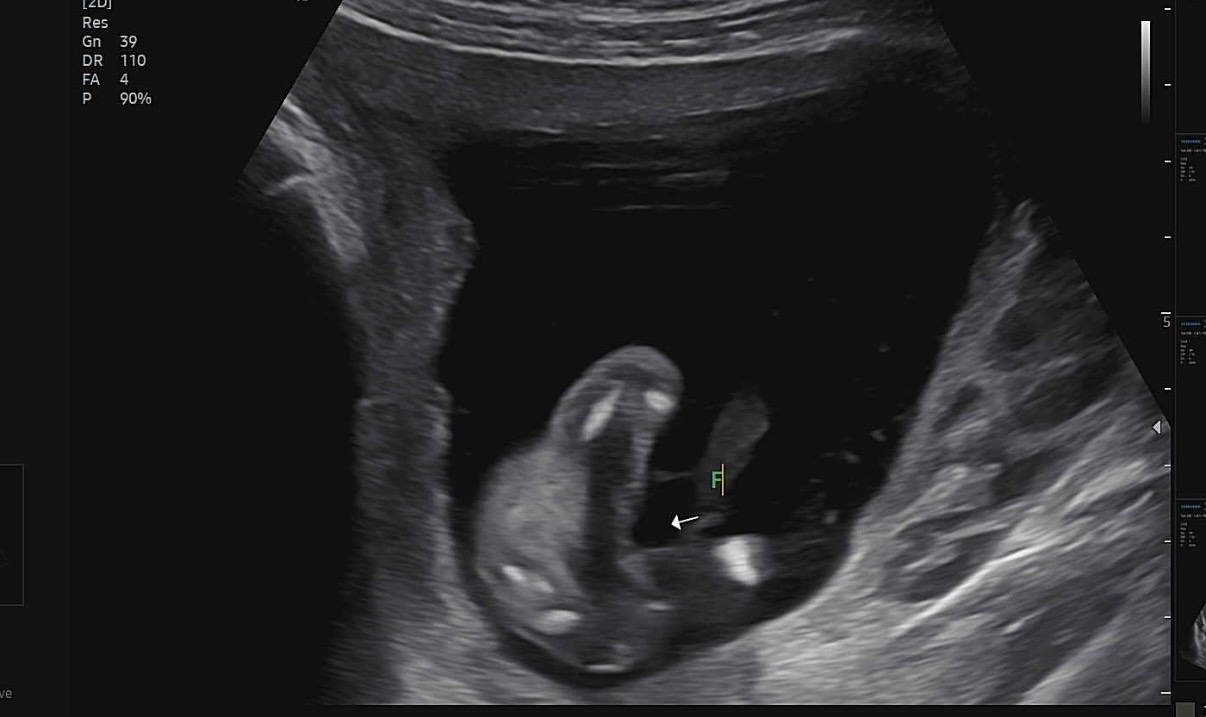

15주 5일 성별 봐주세요 !

애기가 앉아있는 자세로있어서 다리사이가 잘 안보였는데 허벅지 사이가 매끈해서 초음파선생님이 딸 같다고 하시긴했는데 혹시 바뀔수도있을까요..?

딸이네용! 저는16주에 갔는데 첨에 가운데에 뭐가 있어보였는데 의사쌤이 딸인거 같다 하셔서 긴가민가해 하다가 영상 뒤에 더 돌려보니 매끈한부분이 있더라구요! 저보다 1주 늦으신데 저렇게 매끈한거면 딸 확실한데용

15주에 매끈하면 그대로 딸일거에요!! 축하드려용